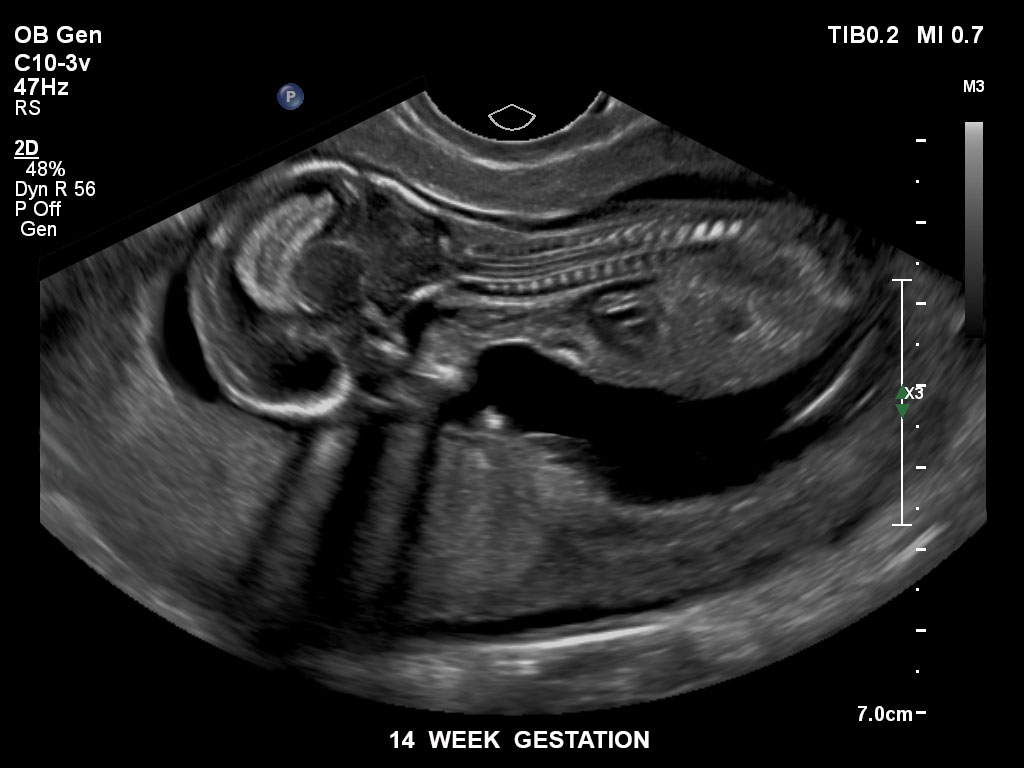

Bildgebung im 1. Trimenon

Überzeugende Bildgebung in allen Schwangerschafts­dritteln

Die EPIQ-Produktreihe mit ausgereiften Schallköpfen erfüllt die Anforderungen auch Ihrer anspruchsvollsten gynäkologischen Untersuchungen und während der gesamten Schwangerschaft.

• C10-3v PureWave-Breitband-Endo-Convex-Schallkopf, ideal für anspruchsvolle Myom- und komplexe Ovar-Untersuchungen sowie Bildgebung im ersten Schwangerschaftstrimester